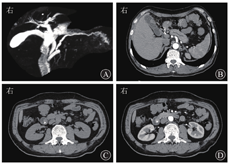

患者入院时精神可,食欲差,1个月内体质量下降5 kg。入院体格检查示上腹部轻压痛,无反跳痛、肌紧张;余未见异常。血常规、尿常规、粪常规、凝血功能指标,以及IL-6水平均在正常范围内,肿瘤标志物(癌胚抗原、CA19-9、甲胎蛋白)均未见异常。血生物化学检查示:ALT水平为64.3 U/L,DBil水平为10.7 μmol/L,GGT水平为193.6 U/L,淀粉酶、脂肪酶等均在正常范围内。2019年1月29日MRCP检查结果见胆总管下段近十二指肠乳头区可疑信号,考虑肿瘤性病变可能,伴胰胆管轻度扩张;2月1日腹部增强CT检查结果可见十二指肠乳头占位、胆管引流术后改变(图1)。

初步诊断为十二指肠乳头占位,内镜下鼻胆引流管置入术后;术后病理诊断为十二指肠乳头壶腹部低分化腺癌。